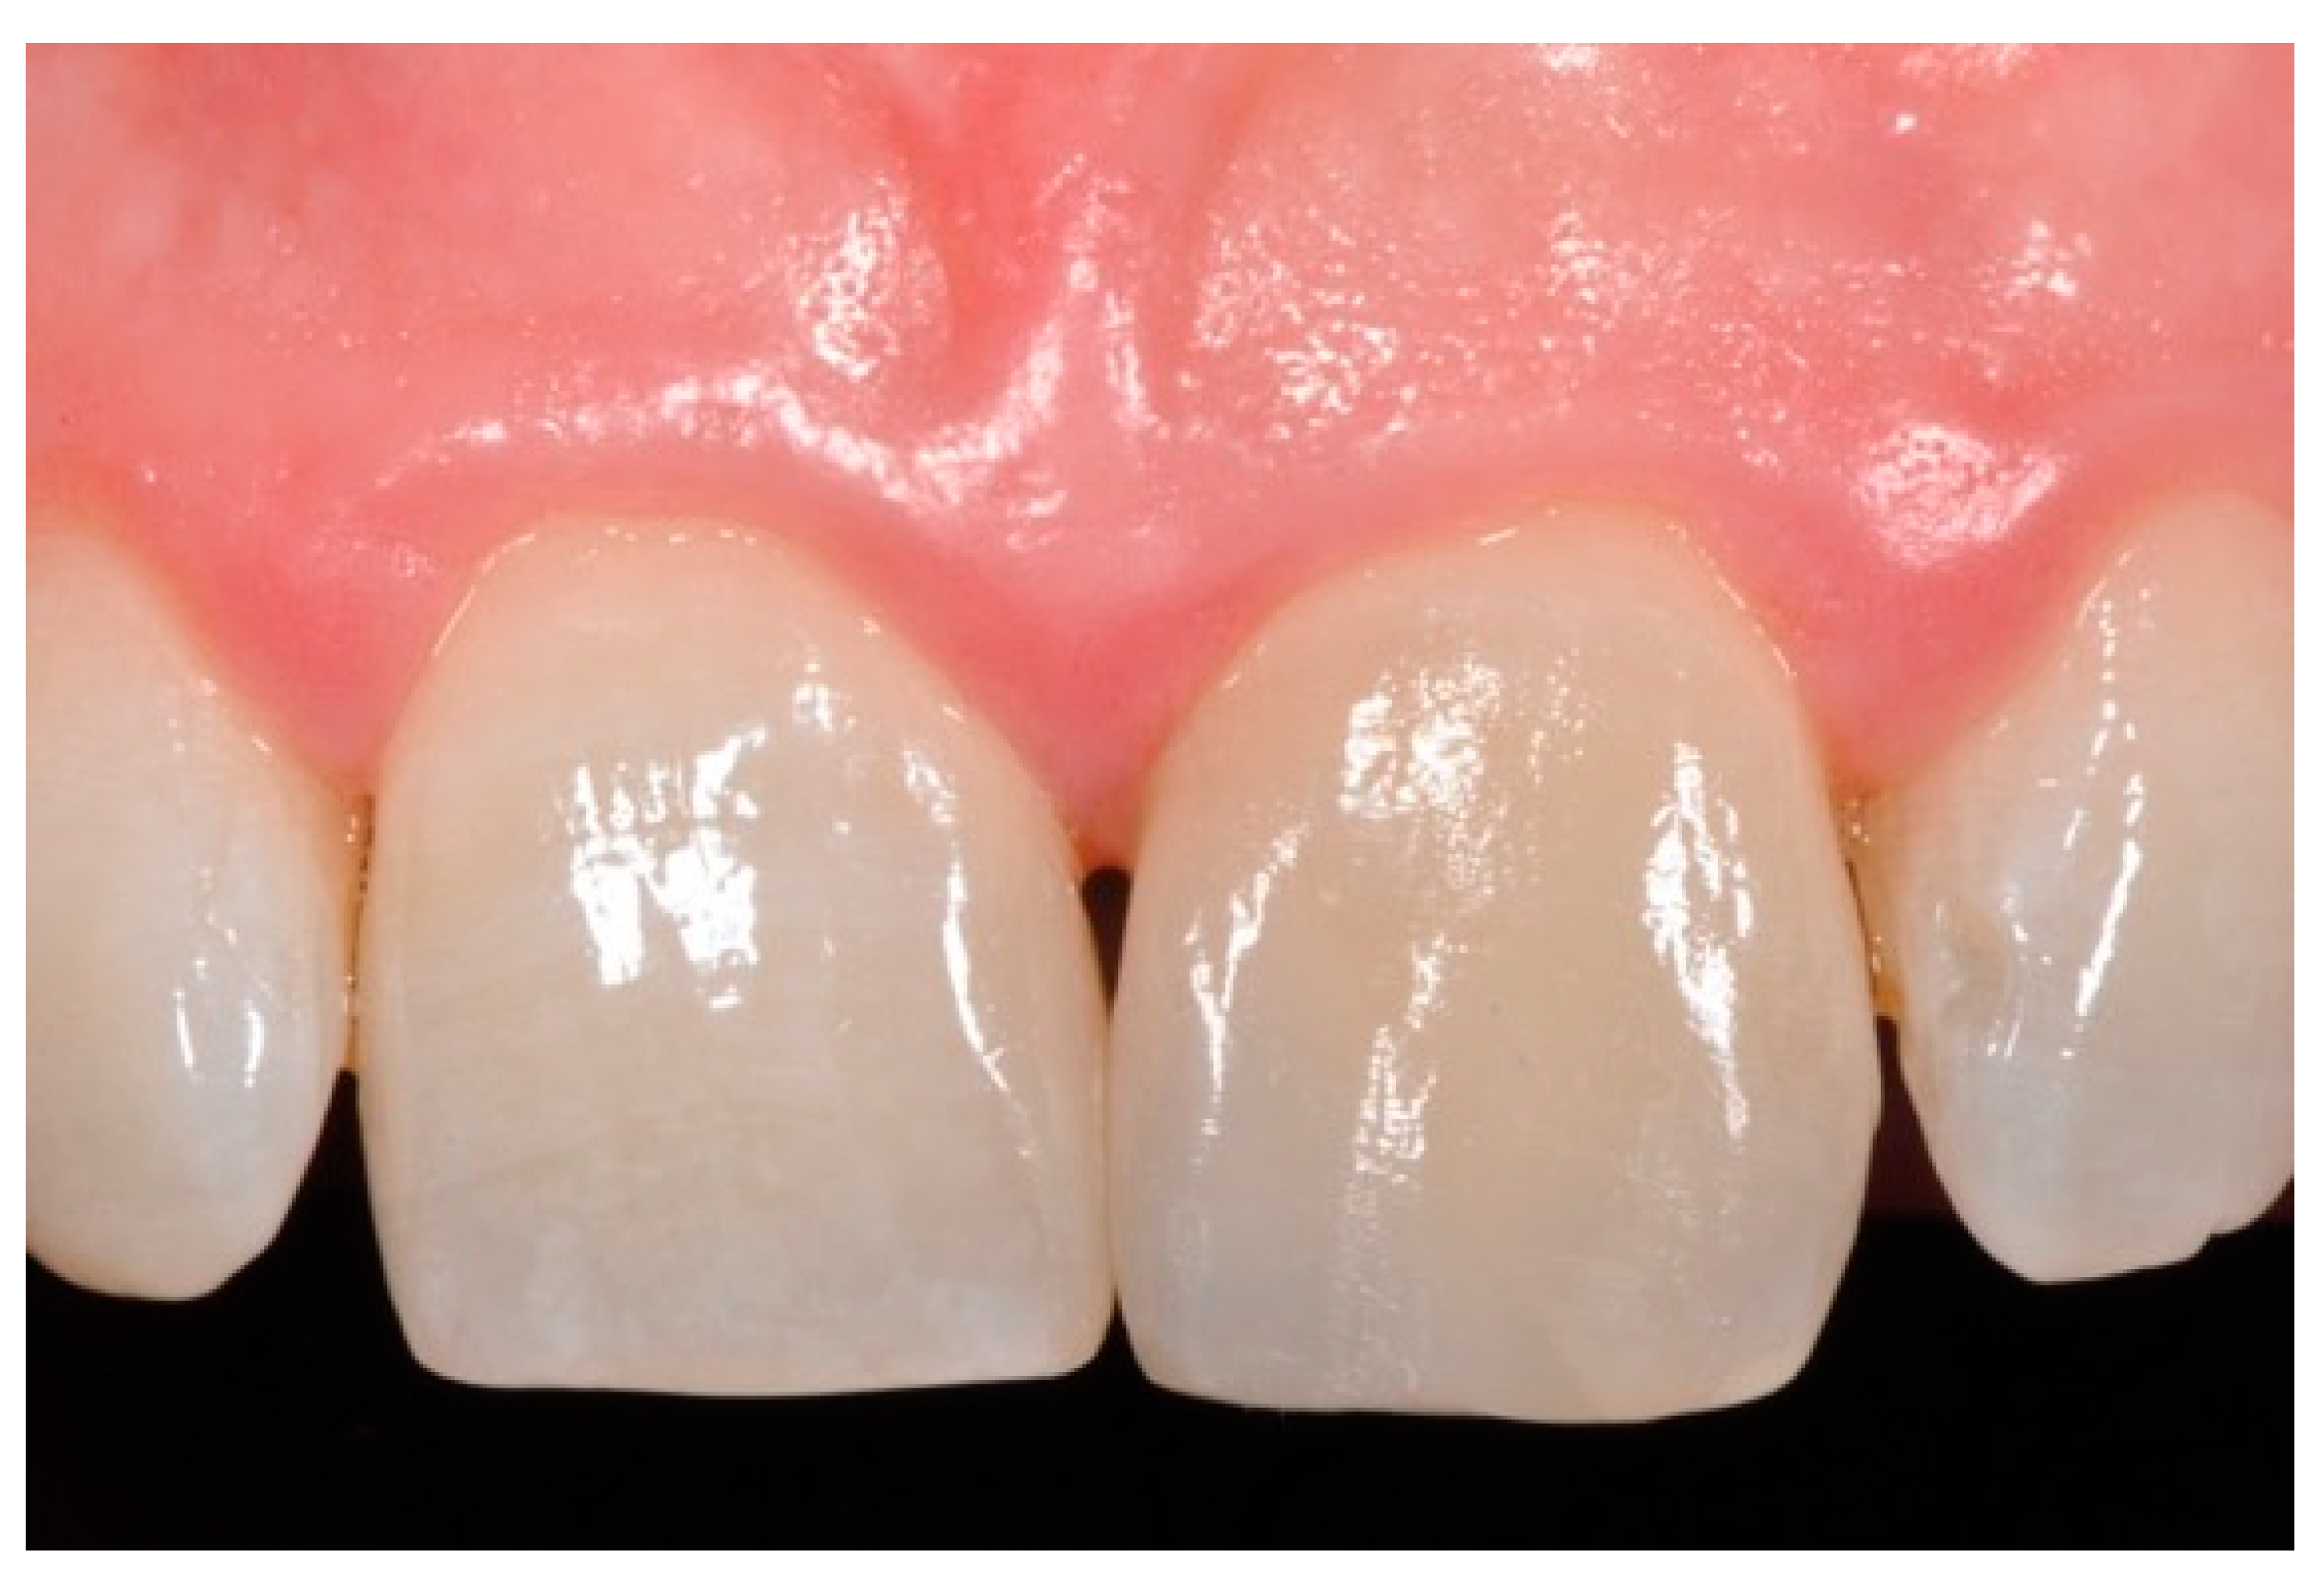

Figure 18.

Five years post-operative.

Figure 19.

Five years post-operative x-ray.